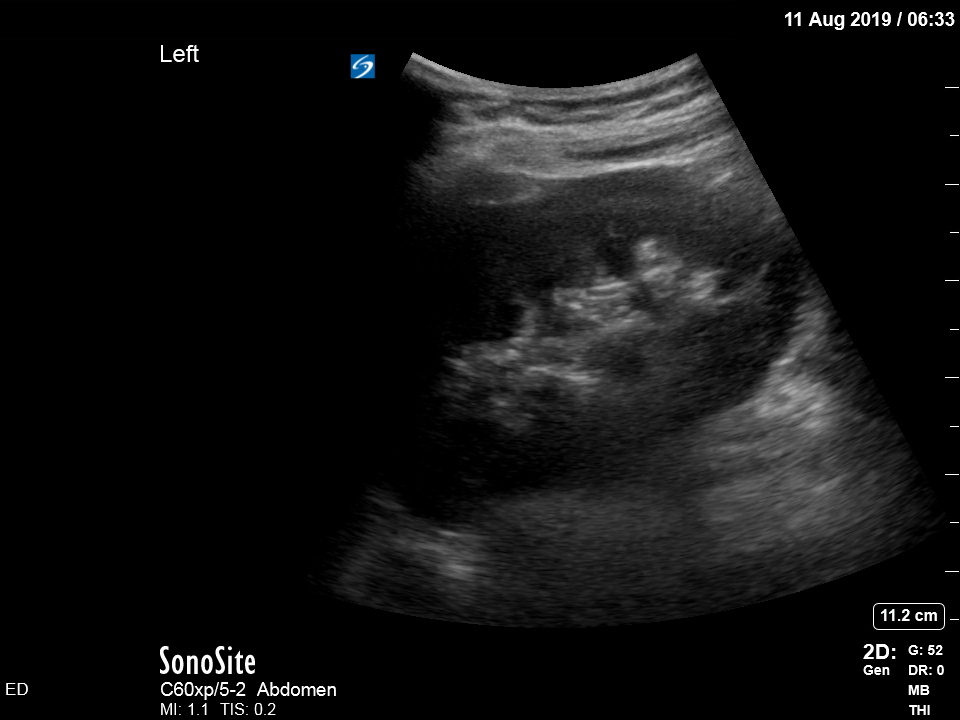

The treating house officer suspected an alternative pathology and bedside ultrasound was performed.

The appearance is typical of acute cholecystitis. The patient was started on IV antibiotics. Images were shown to the surgical registrar who accepted the patient for admission. Formal ultrasound confirmed the findings and the patient went for laparoscopic cholecystectomy within 24hrs. At operation, there was a grossly inflamed gallbladder with an 11mm stone in the neck.

Notice the typical appearance of the gallstone – the anterior face reflects ultrasound producing a hyperechoic (bright) surface. Because no sounds waves pass through the stone, the area behind it cannot be imaged and instead we see the artefact known as posterior acoustic shadow.